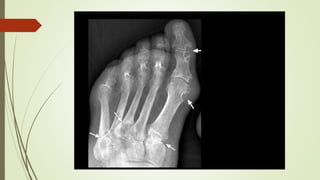

- Radiografia: lesão em saca-bocado

. Evidência de dano radiográfico (saca bocado)

 Diagnóstico - Monoartrite:punção articular!!! (artrocentese) - Clínico + análise de líquidos sinovial ou de bursa  microscopia de luz polarizada  cristais em formato de agulha, com birrefringência negativa - Radiografia: lesão em saca-bocado - USG: sinal do duplo contorno